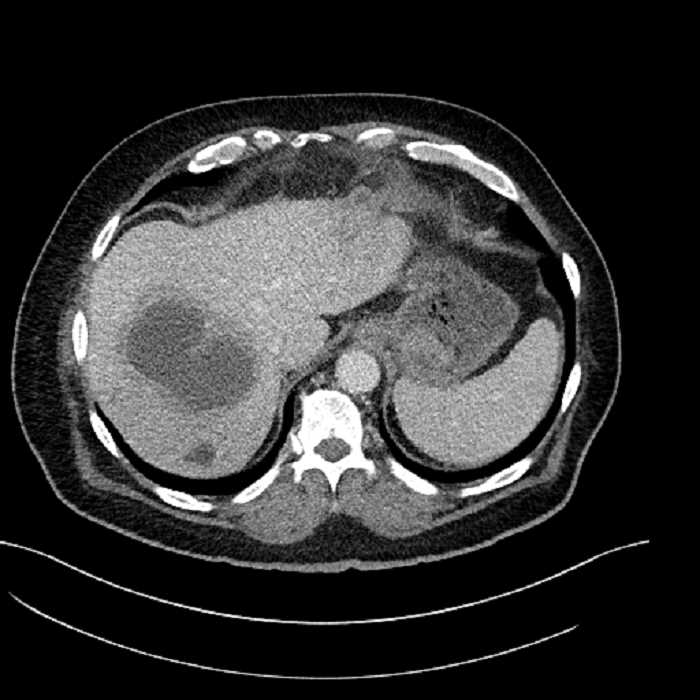

• Large fluid density structure in hepatic segments 7 and 8 measuring 10 x 7 x 7 cm with internal septation and circumferential ill-defined low density compatible with edema

Acute sigmoid diverticulitis complicated by a small contained perforation and a large abscess in the right hepatic lobe. Additional small subcapsular abscesses along the anterior margin of the left hepatic lobe.

• The classic CT imaging appearance is a double target sign with internal low density surrounded by an internal enhancing rim (capsule) and a low density external rim (edema)

Hepatic abscess showing the double target sign with low density internally surrounded by a thin inner enhancing rim (red arrow) and ill-defined outer low density rim (yellow arrow). Blue arrow indicates an internal septation. Red arrows: additional smaller subcapsular abscesses. Red arrow: focal contained perforation associated with diverticulitis.